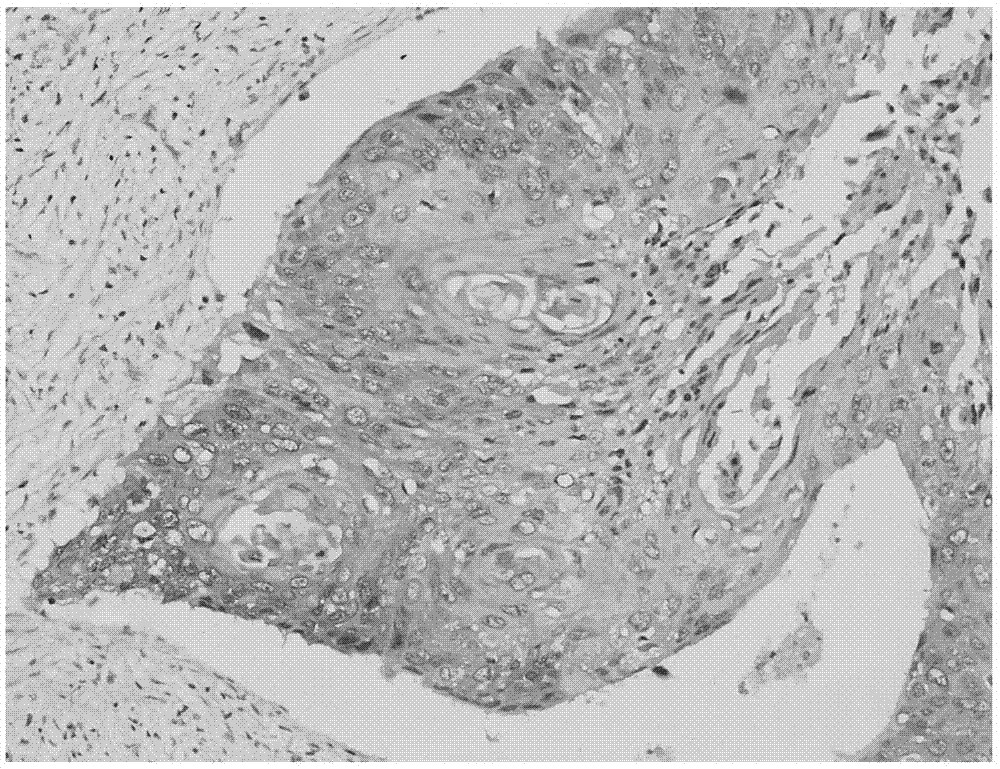

一种AP-Red染色液及其制备方法